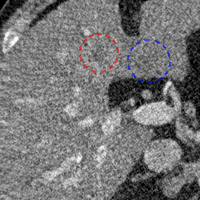

To show the denoising effect of the selected networks, we took two representative slices as shown in Figs. 5 and 7. And Figs. 6 and 8 are the zoomed regions-of-interest (ROIs) marked by the red rectangles in Figs. 5 and 7. All the networks demonstrated certain denoising capabilities. However, CNN-MSE blurred the images and introduced waxy artifacts as expected, which are easily observed in the zoomed ROIs in Figs. 6e and 8e. WGAN-MSE was able to improve the result of CNN-MSE by avoiding over-smooth but minor streak artifacts can still be observed especially compared to CNN-VGG and WGAN-VGG. Meanwhile, using WGAN or GAN alone generated stronger noise (Figs. 6g and 8g) than the other networks enhanced a few white structures in the WGAN/GAN generated images, which are originated from the low dose streak artifact in LDCT images, while on the contrary the CNN-VGG and WGAN-VGG images are visually more similar to the NDCT images. This is because the VGG loss used in CNN-VGG and WGAN-VGG is computed in a feature space that is trained previously on a very large natural image dataset [48]. By using VGG loss, we transferred the knowledge of human perception that is embedded in VGG network to CT image quality evaluation. The performance of using WGAN or GAN alone is not acceptable because it only maps the data distribution from LDCT to NDCT but does not guarantee the image content correspondence. As for the lesion detection in these two slices, all the networks enhance the lesion visibility compared to the original noisy low dose FBP images as noise is reduced by the different approaches.

As for iterative reconstruction technique, the reconstruction results depend greatly on the choices of the regularization parameters. The implemented dictionary learning reconstruction (DictRecon) result gave the most aggressive noise reduction effect compared to the network outputs as a result of strong regularization. However, it over-smoothed some fine structures. For example, in Fig. 8, the vessel pointed by the green arrow was smeared out while it is easily identifiable in NDCT as well as WGAN-VGG images. Yet, as an iterative reconstruction method, DictRecon has its advantage over post-processing method. As pointed by the red arrow in Fig 8, there is a bright spot which can be seen in DictRecon and NDCT images, but is not observable in LDCT and network processed images. Since the WGAN-VGG image is generated from LDCT image, in which this bright spot is not easily observed, it is reasonable that we do not see the bright spot in the images processed by neural networks. In other words, we do not want the network to generate structure that does not exist in the original images. In short, the proposed WGAN-VGG network is a post-processing method and information that is lost during the FBP reconstruction cannot easily be recovered, which is one limitation for all the post-processing methods. On the other hand, as an iterative reconstruction method, DictRecon algorithm generates images from raw data, which has more information than the post-processing methods.